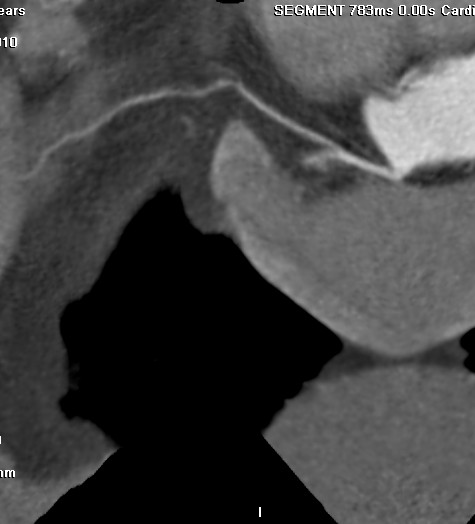

标题: CT24400:患者54岁,心前区不适进行心脏冠脉造影检查。 [打印本页]

标题: CT24400:患者54岁,心前区不适进行心脏冠脉造影检查。

患者54岁,心前区不适进行心脏冠脉造影检查。高手看看有问题没有?

图像很漂亮,好像未见异常